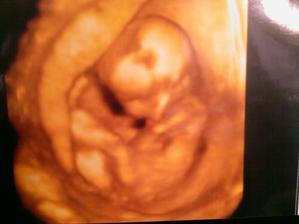

2.2. - drobcek ma 4,2 cm a vsetko je ok. tesime sa a mame aj prvu fotecku :o)...netrpezlivo cakame dalsiu poradnu 2.3.

2.3. - drobcek nam narastol, vsetko je ok :o)